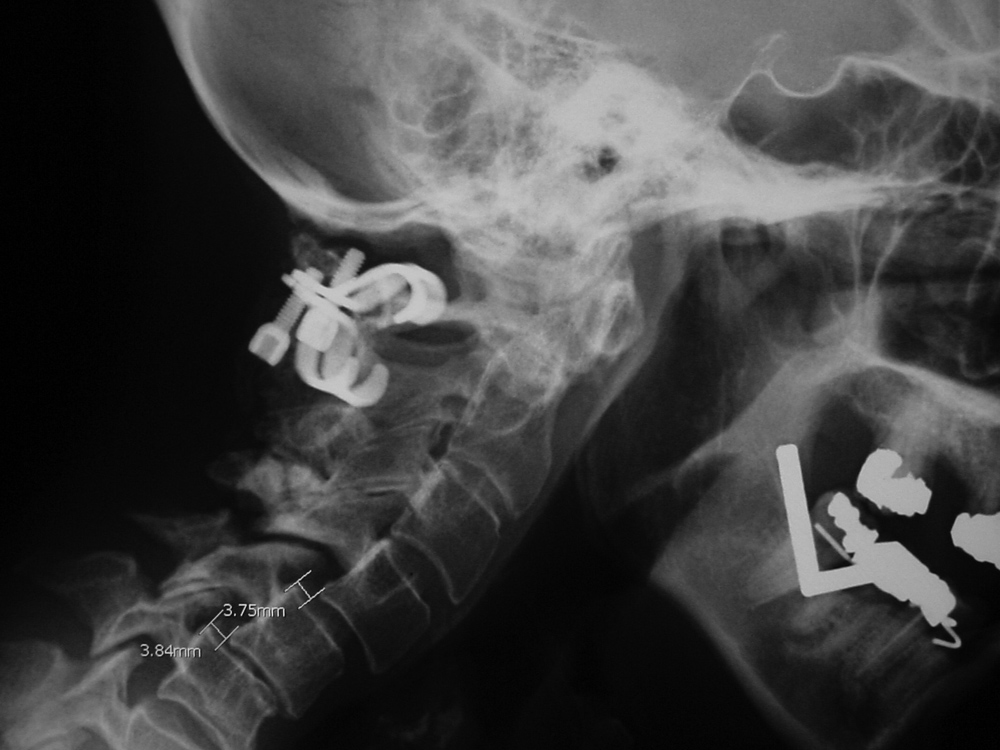

The disk cage is probably composed of PEEK.   Patient with rheumatoid arthritis and atlantoaxial (C1-C2) subluxation and generalized cervical spine laxity Postoperative lateral radiograph of the cervical spine. There is fixation of an odontoid base fracture by an odontoid screw and a sublaminar wire between C1 and C2. There are also skin staples and a surgical drain in the posterior aspect of the neck.

Odontoid screw (nail) AP view Odontoid screw (nail) lateral view Odontoid screw (nail) fracture fixation with posterior cervical fixation plates and screws [extension view] Odontoid screw (nail) fracture fixation with posterior cervical fixation plates and screws [flexion view]

Odontoid screw AP view Odontoid screw lateral view Odontoid screw (nail) fixation with posterior cervical plates and screws Odontoid nail flexion view

There is also an anterior cervical fusion plate and screws from C3-6.